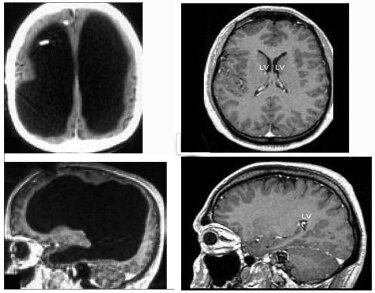

A 44 year old man goes to his doctor as he has had a weak left leg for the past two weeks. He has had no previous medical anomalies, except for one- as an infant, he had hydrocephalus, water in the brain, but this was treated using a stunt, 30 years ago, at the age of 44. While diagnosing his leg pain, the doctors were wary of this fact, and although the stunt had been successful, it had been 30 years, so they ordered an MRI scan, just to be safe. This is what they found:

On the right side is a normal brain- note how it is all filled in. In contrast, his brain (left) was mostly empty- the black spaces are Cerebrospinal fluid; this man had been living his entire life with a brain filled with water.

Although he was no genius, this man was still able to live relatively fine; his IQ was tested to be 75, and he worked as a civil servant. This is quite unusual and surprising, as most people who experience this type of damage in a short amount of time would have died. In this case, the damage was likely done over a long period of time, which would have allowed for his brain to adapt and rewire.